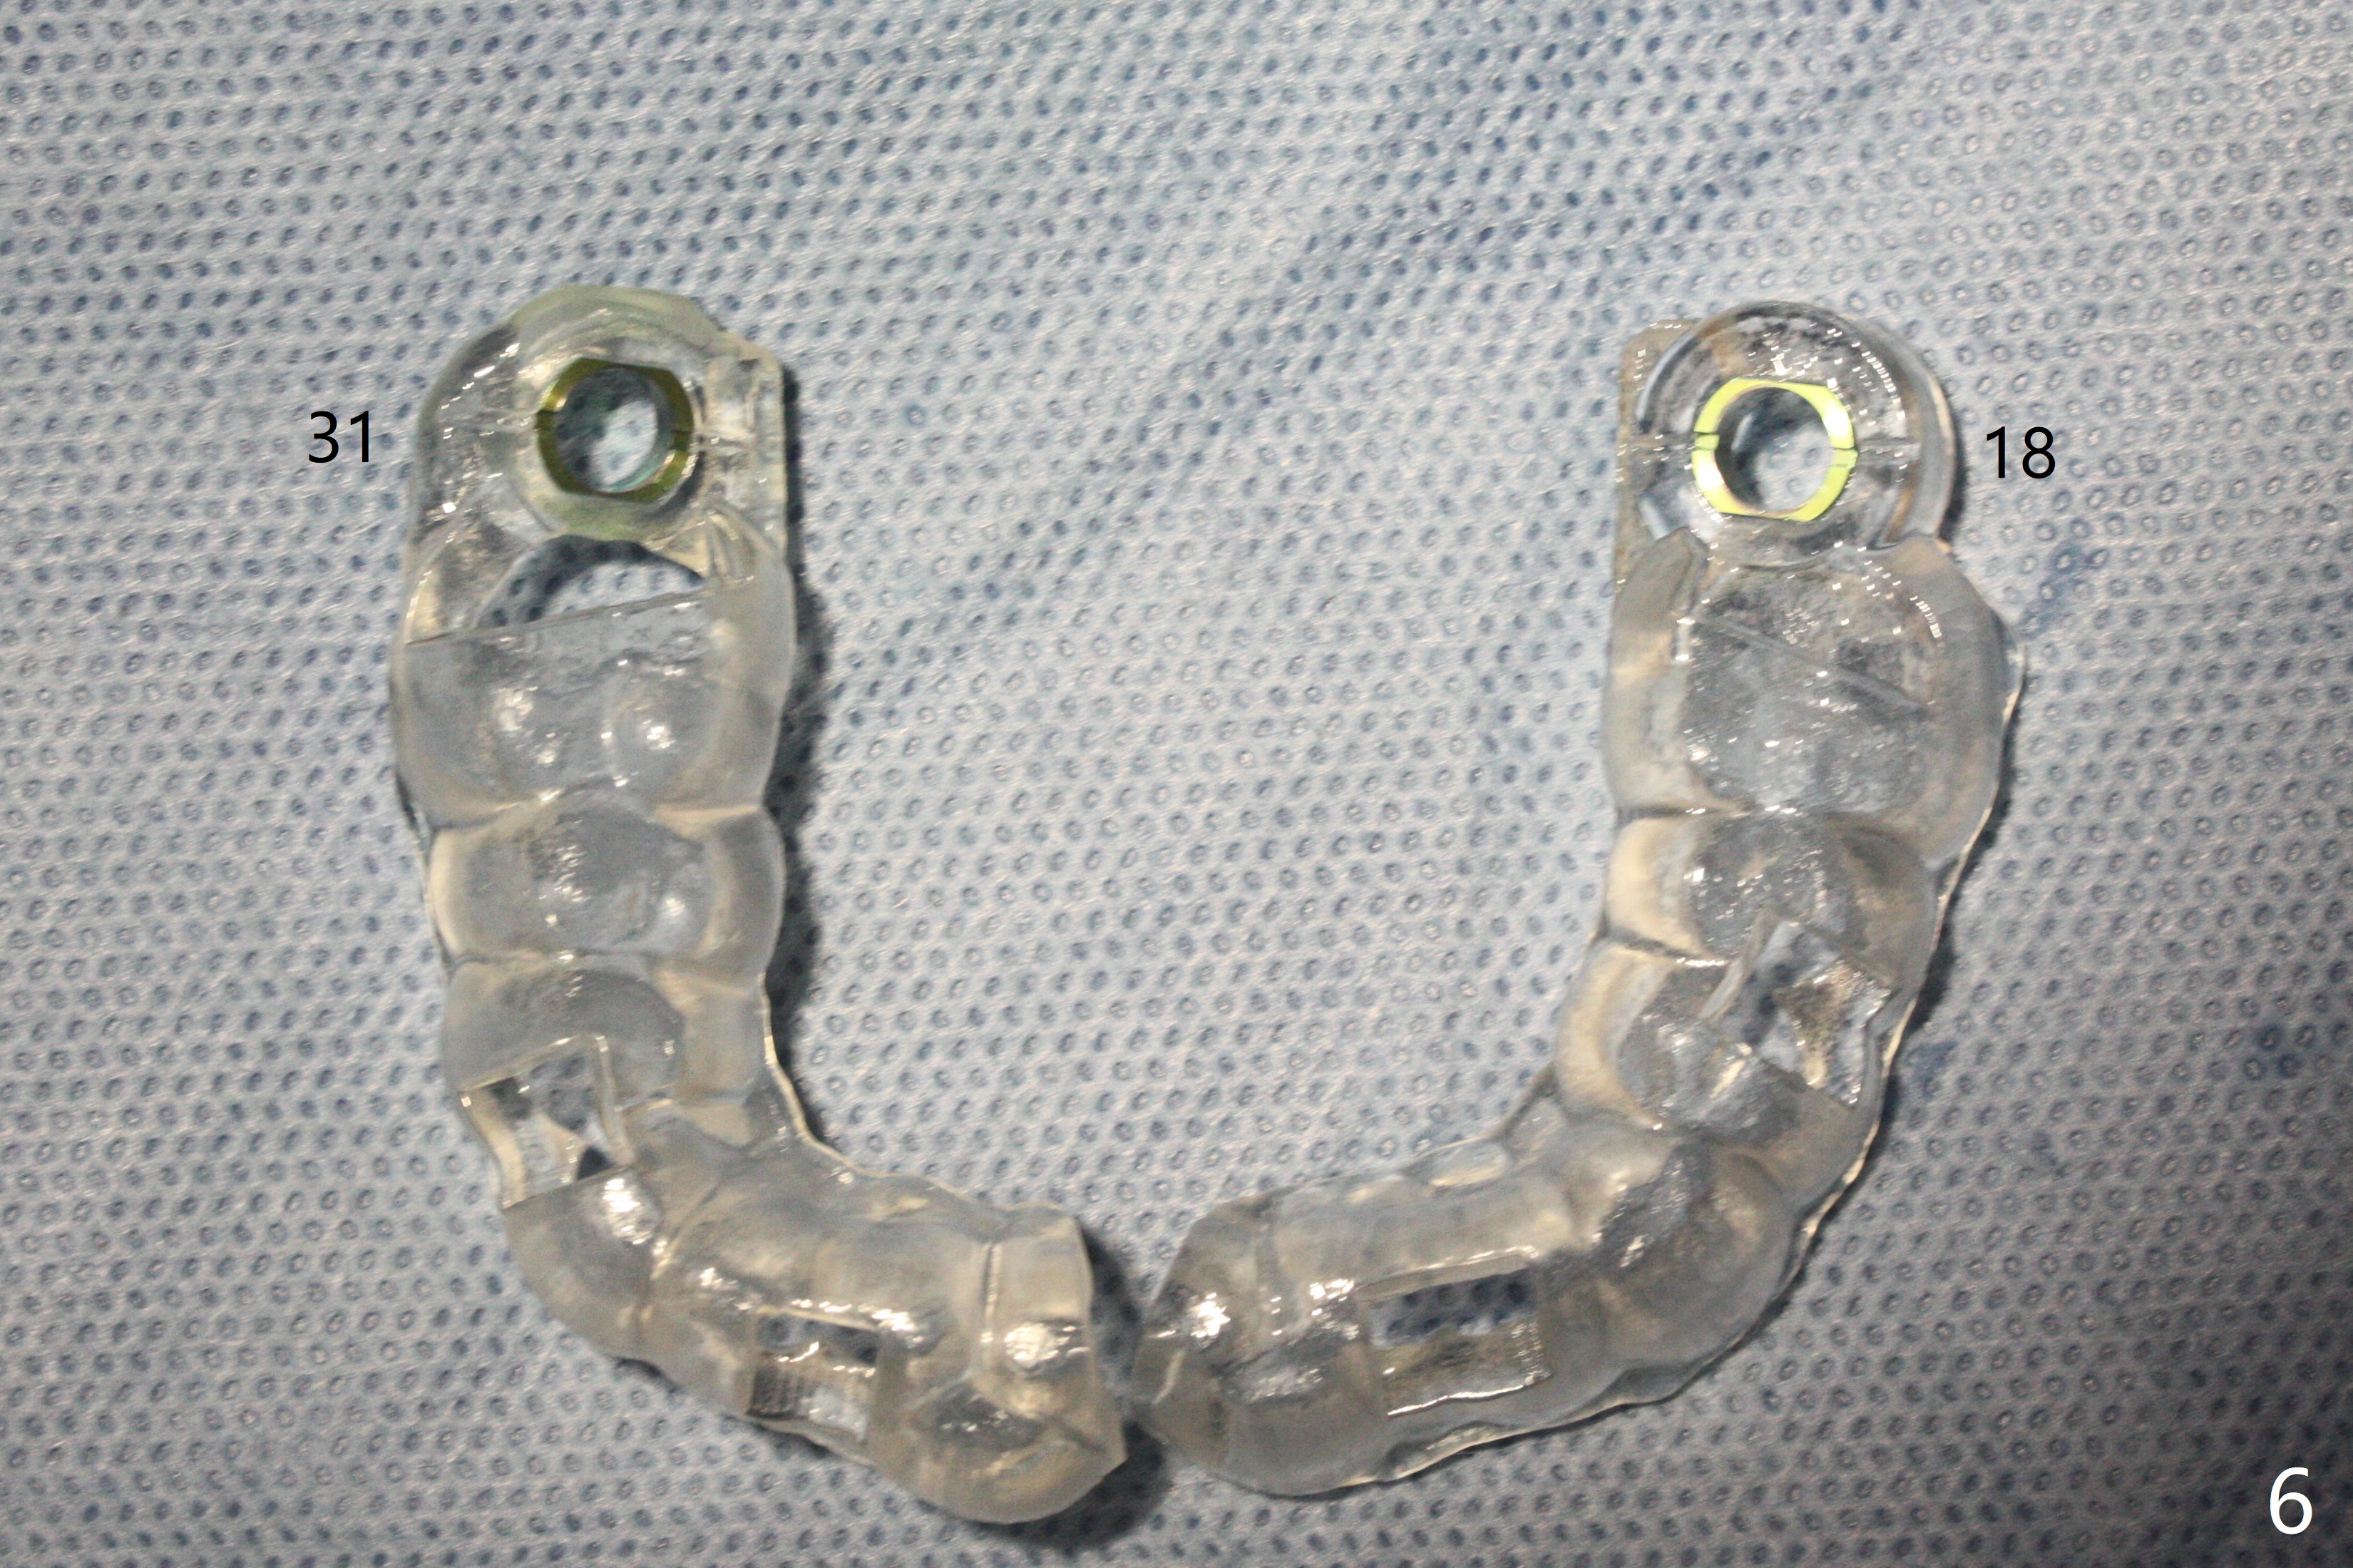

31号牙拔除前近中颊侧有一个瘘道(图一:<),说明32号牙被感染可能性小。术中发现虽然一小部分智齿牙冠与第二磨牙巨大牙槽窝相通(图二:*),但是病变并没有往智齿周围发展(S(可能是牙囊));借助导板(9毫米offset)毫无困难完成钻洞,但是嫌钻洞深度不够。由于植体扭力低(<10 Ncm),只好放置粘性骨粉(图三),覆盖PRF和Cytoplast,PTFE缝线,以及树脂敷料。病人左下第二磨牙缺失多年,牙槽嵴粘膜出现白色病变(图四:箭头),可能与对合磨牙延申有关(图五:箭头)。如果这个牙位需要导板植牙,垂直距离将是一个严峻问题。即种导板(图六:31)与延期导板(18)金属圈放置有不同,相差1.5毫米(图七):即种(由于拔牙)金属圈可以放低,而愈合牙位(由于牙龈存在)金属圈必须放高。所以第二磨牙即种有足够垂直空间优势。术后一周复诊,老的树脂敷料不牢(因为下面没有基台),脱落,下面不可吸收膜没有外翻,重新制作敷料(图八:A)。术后一个月由于2,3号牙之间牙周炎发作,树脂敷料牢靠,下面不可吸收膜稍微暴露,两者取出后,植体略微暴露。没有基台,骨粉固定好像不佳。